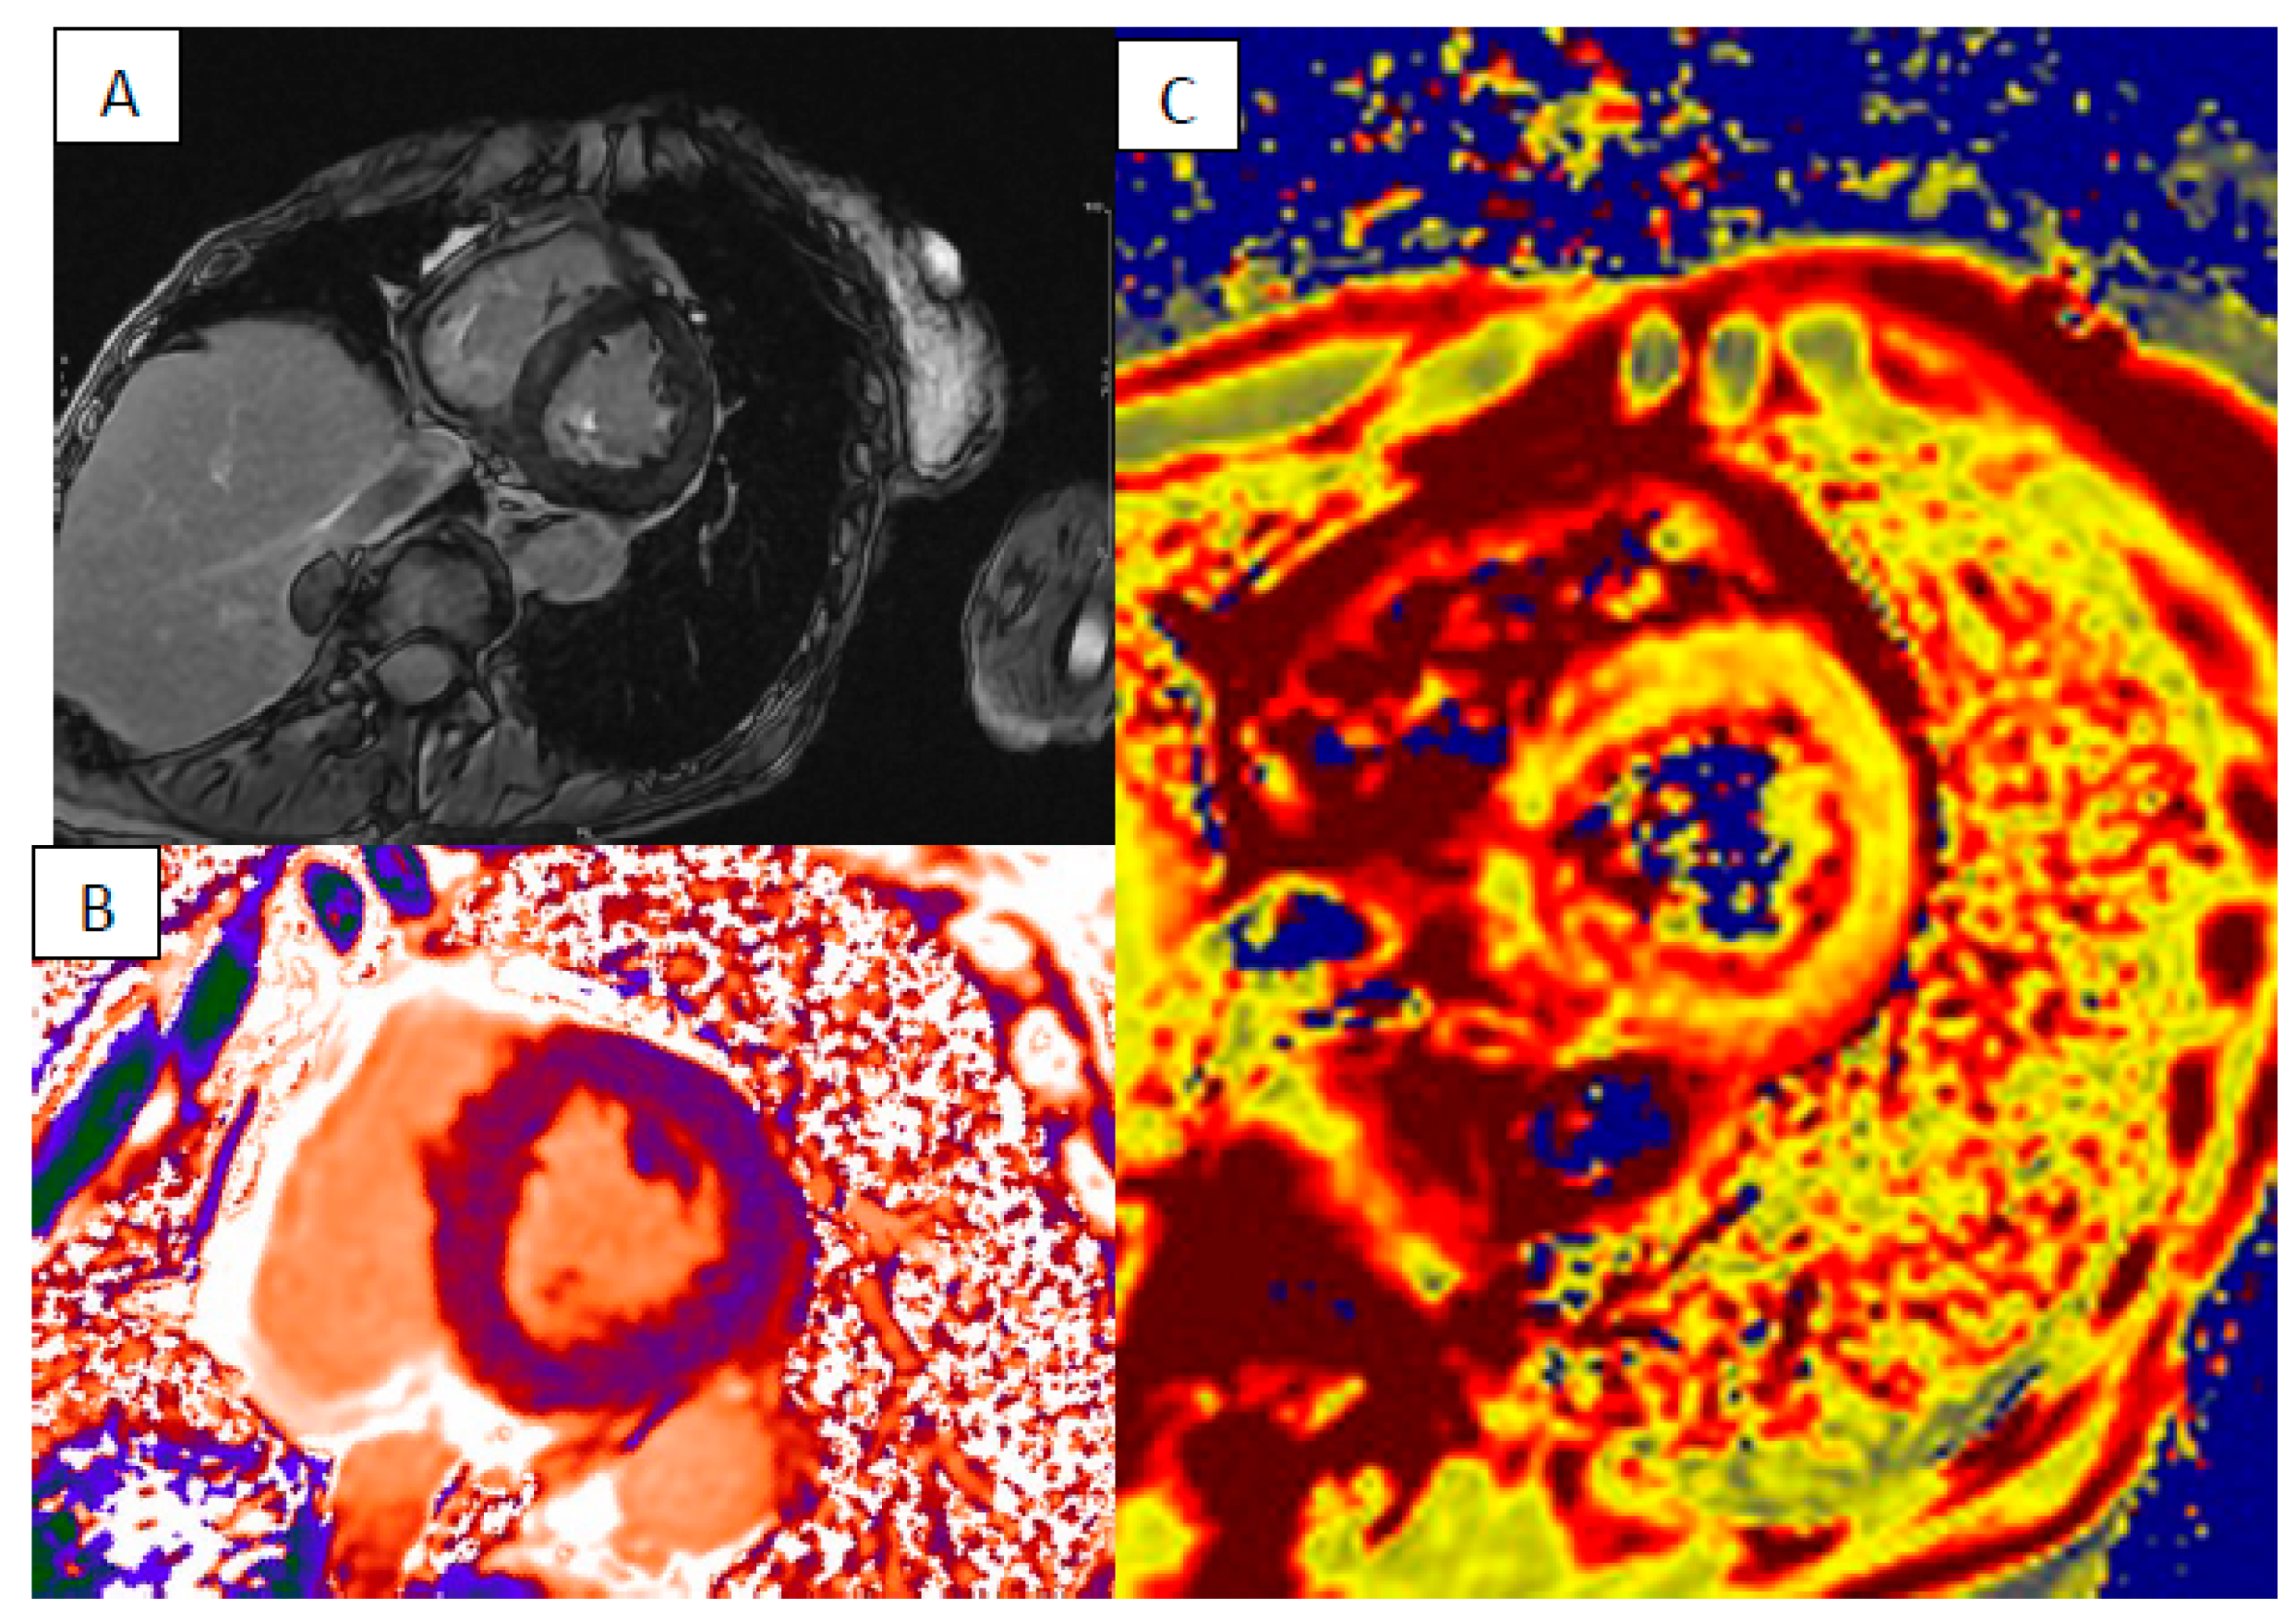

6. Myocardial Iron Overload